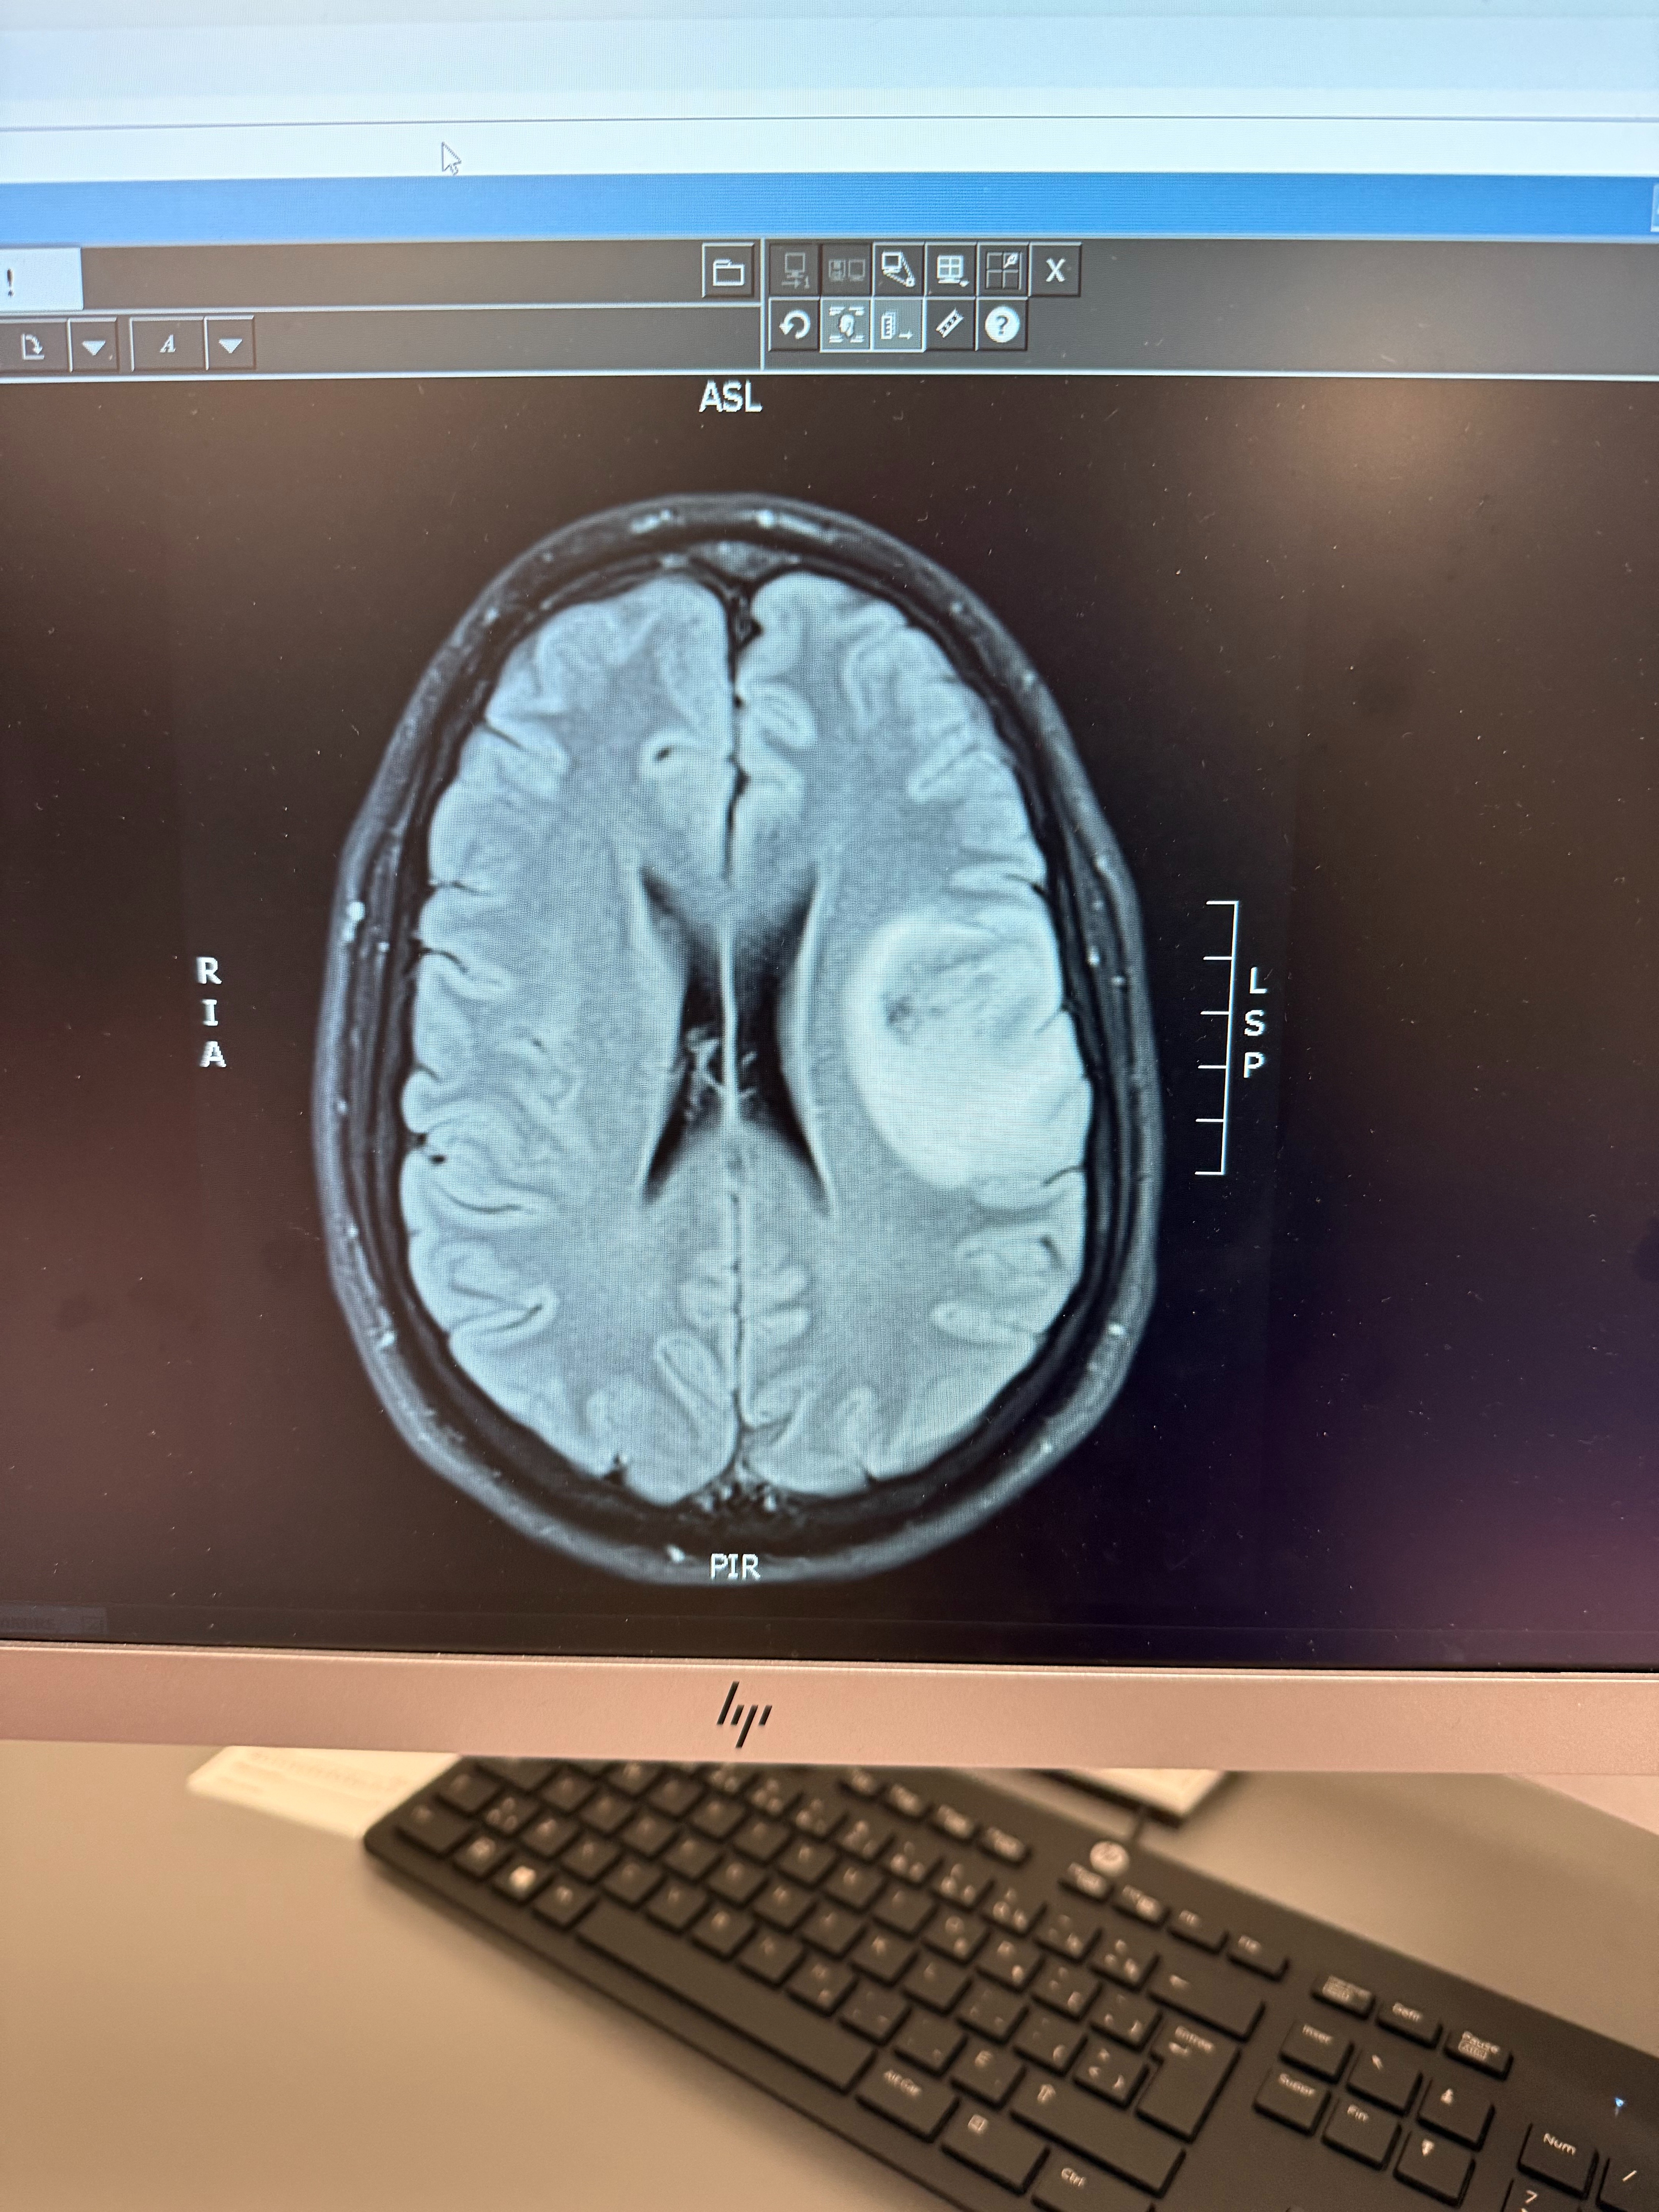

Marc-André, 31 ans, est atteint d’une tumeur au cerveau de grande taille. Les médecins doivent agir rapidement. Il sera opéré au cerveau ce vendredi 6 février, dans seulement quelques jours, en raison de l’urgence.

La tumeur est localisée dans la partie du cerveau qui contrôle des fonctions vitales liées à la parole et à la motricité. Marc-André devra subir une chirurgie éveillée afin de réduire au maximum les risques de séquelles permanentes. L’objectif de l'opération est de retirer le plus de tumeur possible tout en préservant les fonctions essentielles du cerveau.

Ils n’ont pas pu retirer la tumeur à 100 %, afin de préserver ses fonctions vitales et éviter des dommages irréversibles.